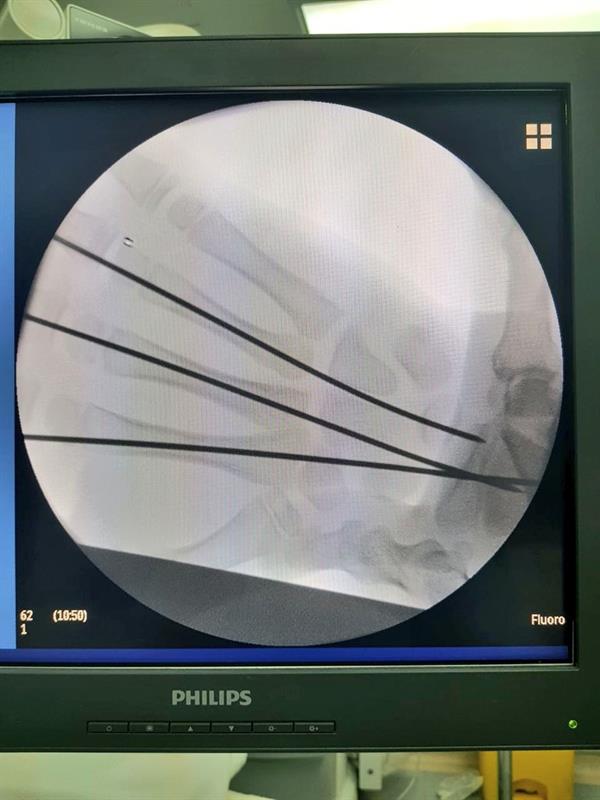

في مستشفى أبوعريش العام، تمكن فريق طبي متخصص من إجراء جراحة عاجلة ونادرة لطفل تعرض لحادثة مرورية نتج عنها خلع مشطيات اليد اليمنى بشكل كامل، حيث تم خلال الجراحة وإدخال الأسلاك المعدنية «IC.wires» من نهاية المشطيات عن طريق فتحات لا تتجاوز 2ملم وتثبيتها بالرسغ.